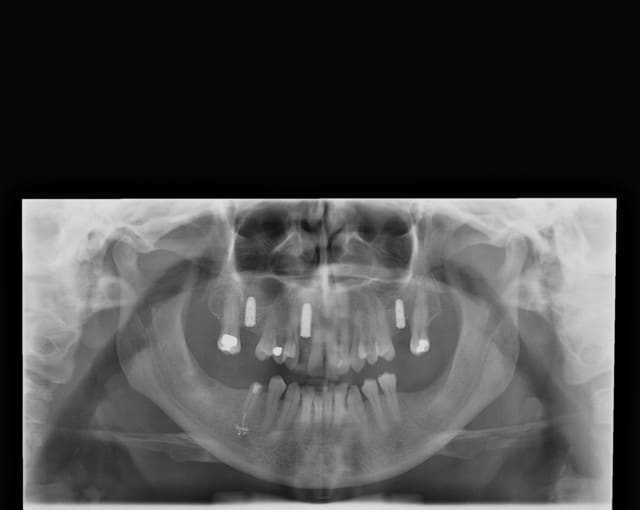

pxav

le pano

Voila mon ami

Vav hen 28.08 - Eugenol

28/08/2009 à 21h43

Merci

Joli.

J'aime aussi bcp le cas avec 3 implants, nice.